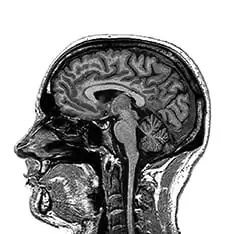

The Neuro ophthalmic clinic focuses on patients experiencing visual disturbances, blurred vision, double vision and abnormal eye movements.

The neuro ophthalmic expertise at Laxmi Eye Hospital is well complemented by advanced diagnostic equipment and sensitive staff who understand that these patients require more than clinical services